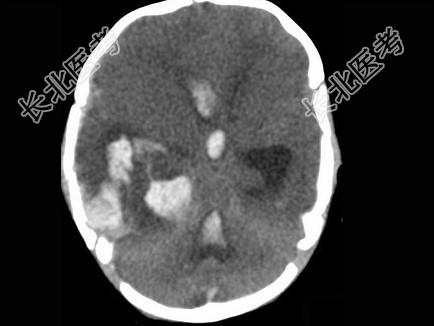

- 单项选择题男,刚满月, 突然发现不进食,昏睡, 无家族遗传病史,结合图像, 最可能的诊断是 ( )

A、脑膜炎

B、脑出血

C、脑脓肿

D、颅内动脉瘤

E、脑梗死